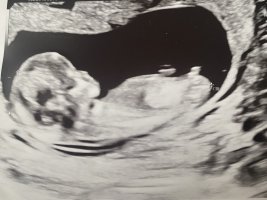

Alt såg bra ut på OTUL 12+3